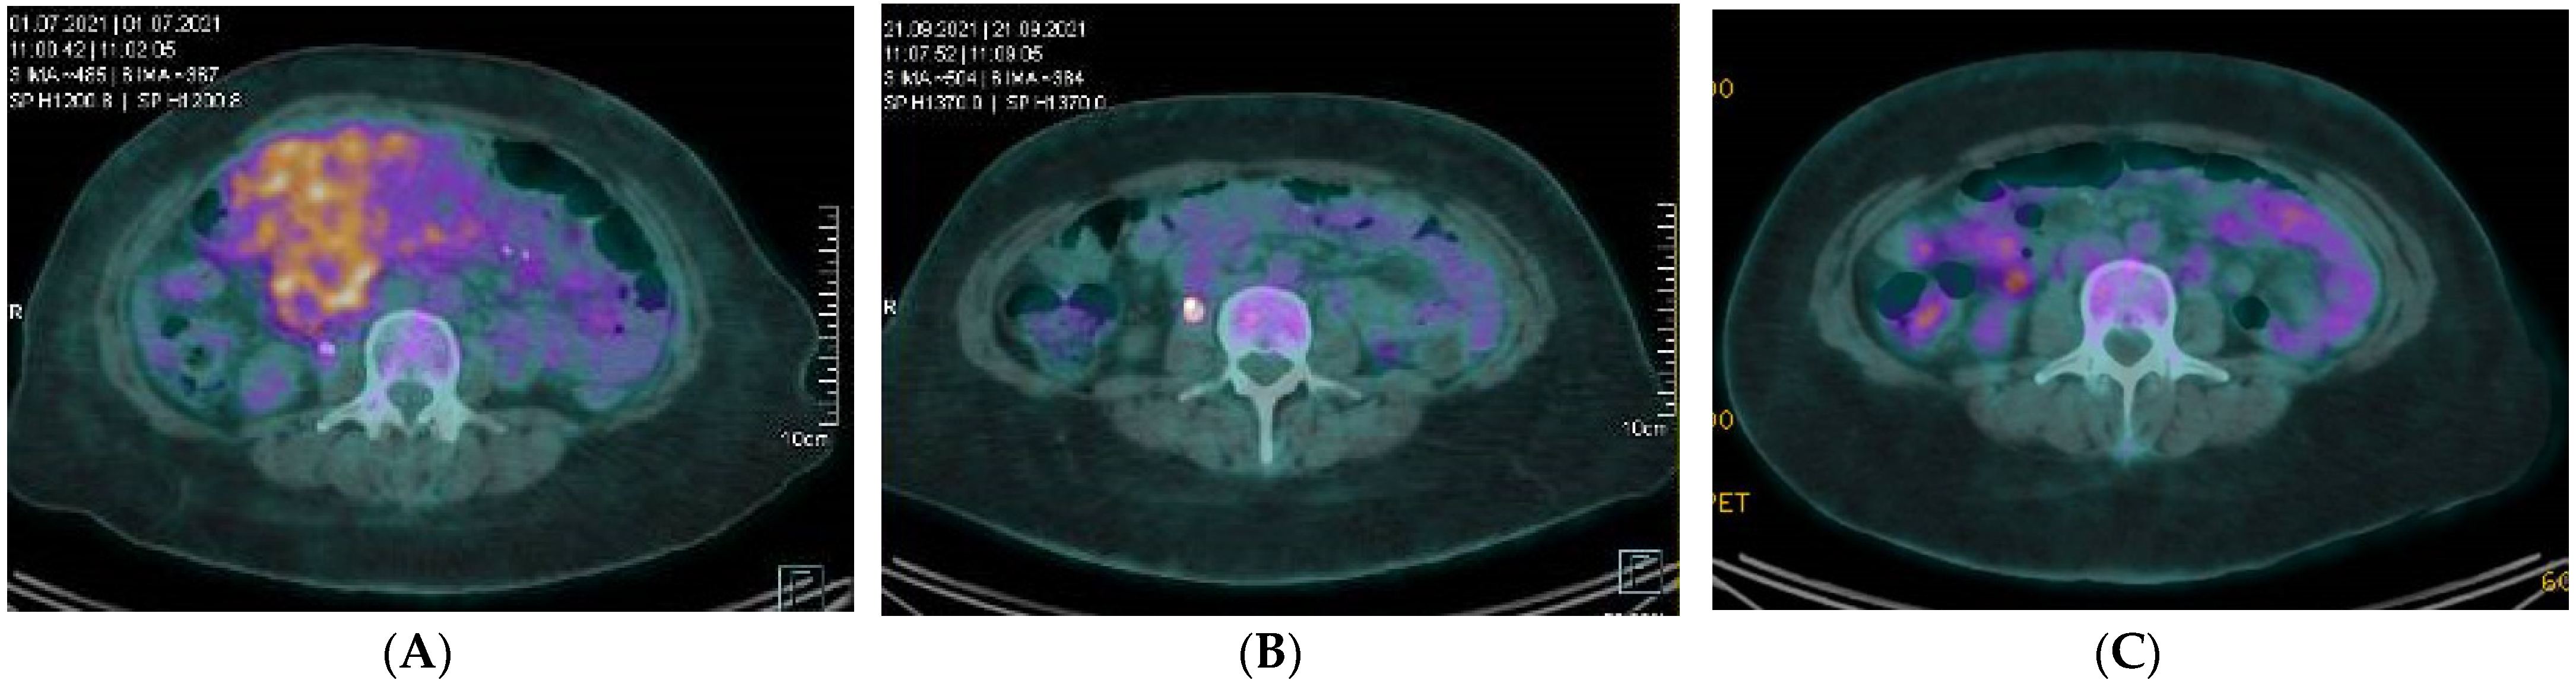

| Current case | 1 | 39 | F | Intraabdominal | ALKi (Alectinib) | Yes | Nuclear membrane | RANBP2-ALK |